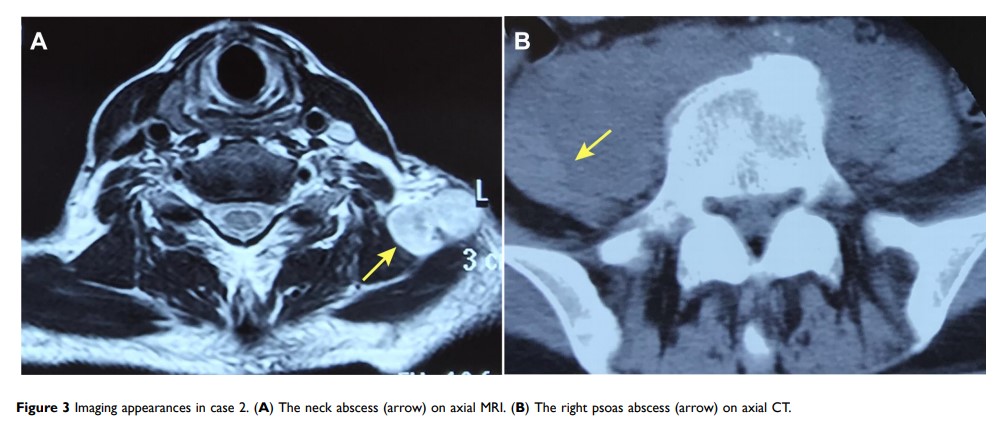

原发性骨髓纤维化患者接受鲁索替尼治疗期间的结核病:病例系列和文献综述